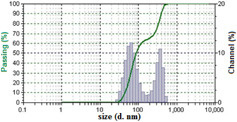

Hesperetin loaded nanoparticles were prepared from Eudragit® E copolymer using nanoprecipitation method. The functional performance of nanoparticles based delivery systems depends on the physicochemical properties of the nanoparticles, such as size, morphology and physical state. Dynamic light scattering analysis revealed that the formulated nanoparticles had an average size of 180 nm (figure 1) with slight positive potential (+ 0.962 mV) (figure 2).

Figure 1. Mean particle size of hesperetin-loaded nanoparticles (HETNPs) measured by dynamic light scattering.

In the present study, hesperetin-loaded nanoparticles were prepared by nanoprecipitation method and its anticancer efficiency in KB oral cancer cells was tested. Particle size of nanoparticles plays a crucial role in their antitumor activity and in vivo distribution [32, 33]. Smaller nanoparticles show a higher accumulation at tumor sites and prolong in vivo half-life due to their avoidable capture by the reticuloendothelial system [34, 35]. From the results of DLS technique, the average particle size is nearly 180 nm. TEM results clearly indicated that particles have nearly spherical shape with an average size of ∼55 nm. The size measured by DLS is that of water-swollen particles (hydrodynamic diameter), whereas the size deduced from TEM measurement corresponds to particles in a dried state. Therefore, the particle size from TEM measurements in a dried state cannot be compared with the values from DLS measurements and DLS gave higher values compared to TEM [36]. Particle size is controlled around 180 nm which is in favor of the antitumor activity and prolongs efficacy of HETNPs. Nanoparticles with small particle size (< 200 nm) are reported to have cross vasculature endothelia and accumulated at tumor sites via the enhanced permeation retention (EPR) effect [23]. It was further established that the optimal particles size is ranging from 20 to 400 nm [37]. Hesperetin-loaded nanoparticles are thus convenient to benefit from the EPR effect. Further, the zeta potential values are close to zero. The factor which might be responsible for such an effect can be the presence of residual PVA on the nanoparticles surface.